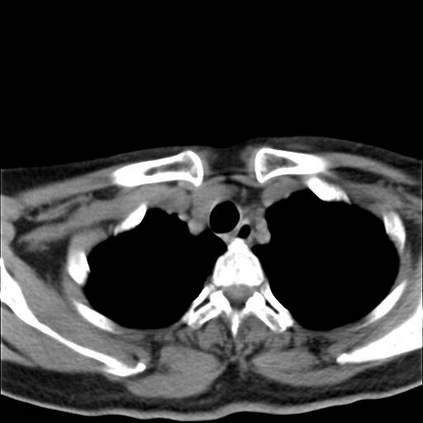

Low-Dose Computed Tomography (LDCT) technique, which reduces the radiation harm to human bodies, is now attracting increasing interest in the medical imaging field. As the image quality is degraded by low dose radiation, LDCT exams require specialized reconstruction methods or denoising algorithms. However, most of the recent effective methods overlook the inner-structure of the original projection data (sinogram) which limits their denoising ability. The inner-structure of the sinogram represents special characteristics of the data in the sinogram domain. By maintaining this structure while denoising, the noise can be obviously restrained. Therefore, we propose an LDCT denoising network namely Sinogram Inner-Structure Transformer (SIST) to reduce the noise by utilizing the inner-structure in the sinogram domain. Specifically, we study the CT imaging mechanism and statistical characteristics of sinogram to design the sinogram inner-structure loss including the global and local inner-structure for restoring high-quality CT images. Besides, we propose a sinogram transformer module to better extract sinogram features. The transformer architecture using a self-attention mechanism can exploit interrelations between projections of different view angles, which achieves an outstanding performance in sinogram denoising. Furthermore, in order to improve the performance in the image domain, we propose the image reconstruction module to complementarily denoise both in the sinogram and image domain.